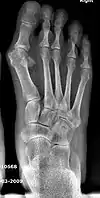

![]() Fig. 8a. Painful hallux valgus and metatarsus primus varus deformities recurrence of left foot after osteotomy surgery | |

- For recurrence correction after osteotomy procedure (Fig. 8)

Late deformity recurrence can happen after osteotomy (bone-breaking) procedures because osteotomy surgeries do not specifically stabilize first metatarsal bone.